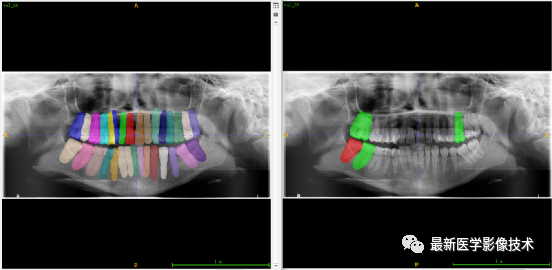

验证集牙齿分割计数和异常牙齿分割识别

左图是分割计数,右图是异常牙齿分割识别结果